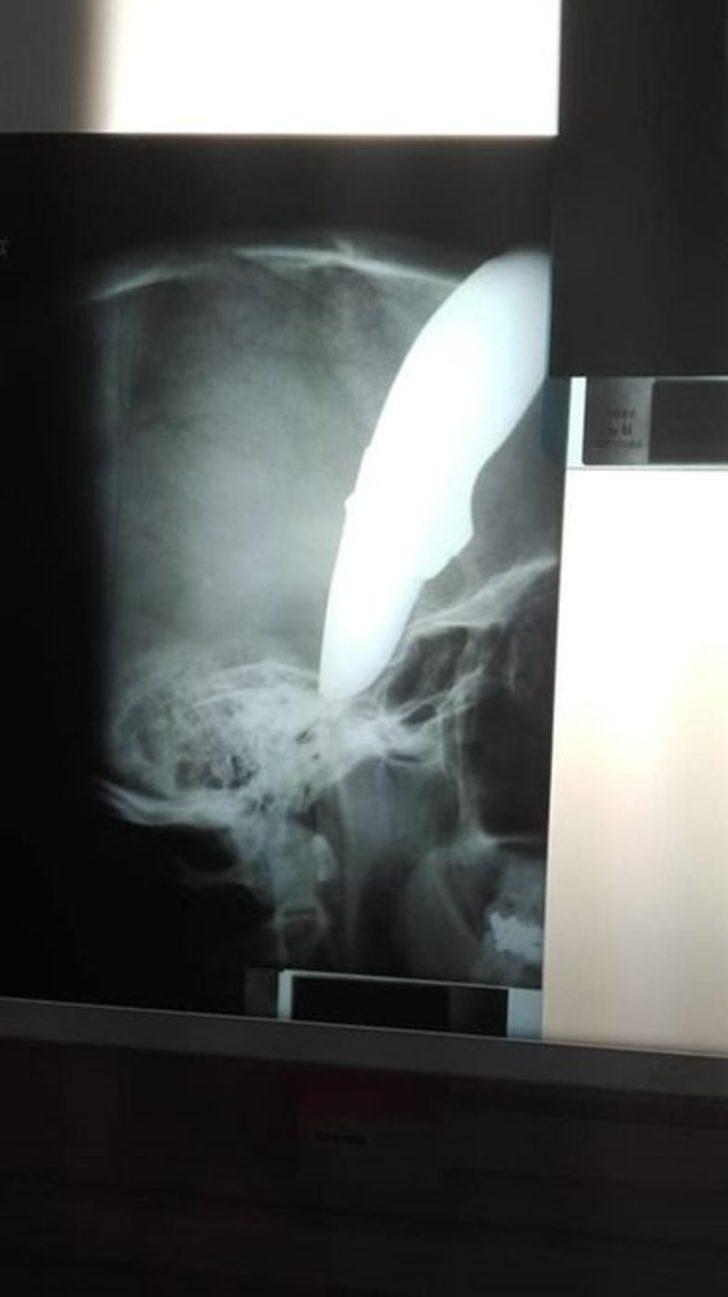

34 yaşındaki Shaun Wayne'i görenler hayretler içinde kaldı. Wayne'in kafatasına saplanmış 15 santimetrelik bir bıçak vardı.

Başına saplanmış 15 cm'lik bıçakla kurtuldu!

Shaun Wayne'i gören doktorlar talihsiz adamı hemen ameliyata aldı. Mucizevi bir şekilde hayatta kalan adamın fotoğrafı ise, sosyal medyada viral oldu.